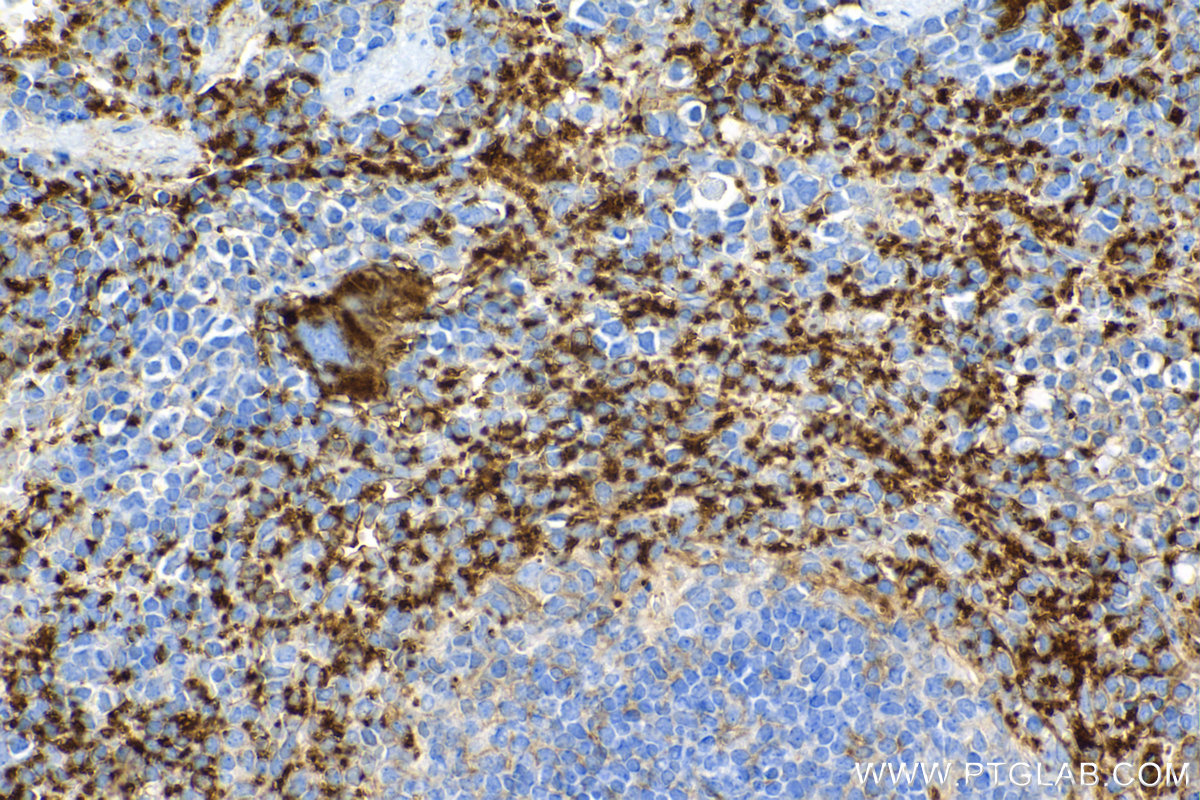

| Positive IHC detected in | mouse spleen tissue, human prostate cancer tissue, mouse kidney tissue, rat spleen tissue Note: suggested antigen retrieval with TE buffer pH 9.0; (*) Alternatively, antigen retrieval may be performed with citrate buffer pH 6.0 |

| Immunohistochemistry (IHC) | IHC : 1:1000-1:4000 |